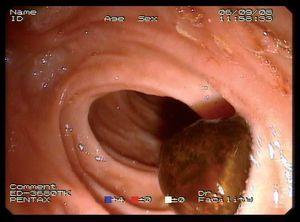

Mujer de 87 años que ingresa en el servicio de cirugía por ictericia, colangitis y pancreatitis aguda. Se instauró tratamiento con sueroterapia y antibióticos, que consiguió la estabilización hemodinámica de la paciente. En una colangiopancreatografía por resonancia magnética (fig. 1) se observó un defecto de repleción en el colédoco distal. Con la intención de desobstruir la vía biliar, se realizó una colangiopancreatografía retrógrada endoscópica (CPRE), empleando sedación consciente con midazolam y dolantina. En la endoscopia, la ampolla de Vater se encontró muy abultada, con un orificio en el que parecía entreverse una coledocolitiasis (fig. 2). Se realizó una esfinterotomía biliar amplia (fig. 3) y se extrajo una coledocolitiasis de 13 mm de diámetro máximo, que estaba impactada en la ampolla (fig. 4). La evolución de la paciente fue satisfactoria.

Fig. 3